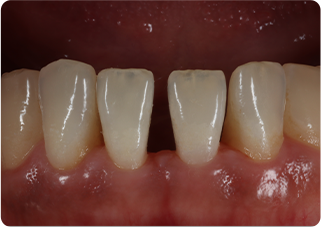

ダイレクトボンディング症例③ 正中離開

術前

ラバーダム防湿

術後

| 主訴 | 下の前歯の隙間が気になる |

|---|---|

| 治療期間/回数 | 2週間、3回 |

| 価格(税込) | 66,000円(税込) |

| リスク・副作用 | コンポジットレジンの破損、一時的な知覚過敏が生じる場合がある |

| ポイント | むし歯ではないので歯を削らずにダイレクトボンディングを行った。歯の形が理想の形になるよう、術前にシリコンインデックスを作成し充填の際に使用。また、充填時にラバーダム防湿を行うことで、詰め物の接着効果が最大限発揮できるようにした。 |